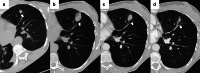

Image-guided percutaneous lung ablation has proven to be a valid treatment alternative in patients with early-stage non-small cell lung carcinoma or oligometastatic lung disease. Available ablative modalities include radiofrequency ablation, microwave ablation, and cryoablation. Currently, there are no sufficiently representative studies to determine significant differences between the results of these techniques. However, a common feature among them is their excellent tolerance with very few complications. For optimal treatment, radiologists must carefully select the patients to be treated, perform a refined ablative technique, and have a detailed knowledge of the radiological features following lung ablation. Although no randomized studies comparing image-guided percutaneous lung ablation with surgery or stereotactic radiation therapy are available, the current literature demonstrates equivalent survival rates. This review will discuss image-guided percutaneous lung ablation features, including available modalities, approved indications, possible complications, published results, and future applications.